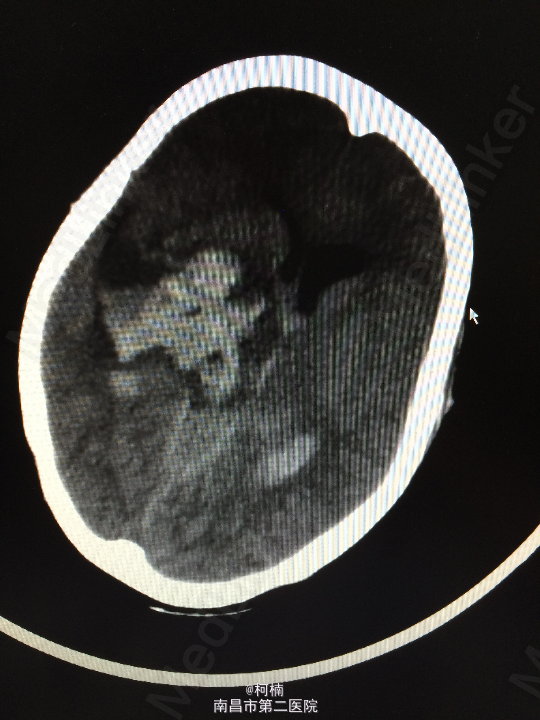

主诉:头痛伴呕吐2天,意识障碍1天 病史:患者于2天前运动后出现头晕头痛,为爆炸样头痛,程度较重,伴呕吐多次,呕吐物均为为内容物,伴四肢乏力,予休息处理。次日清晨患者出现头痛加重,伴呕吐,甚至模糊,呈嗜睡状态,呼之能应,遂急诊送入当地ICU治疗,查头部CT示:蛛网膜下腔出血,予脱水、止血对症治疗后患者症状无明显缓解。转入我院进一步治疗。

查体:神志朦胧,颈抵抗,右侧肢体及躯干深感觉减退,左侧正常。 辅助检查:复查CT提示左侧额叶出血破入脑室系统